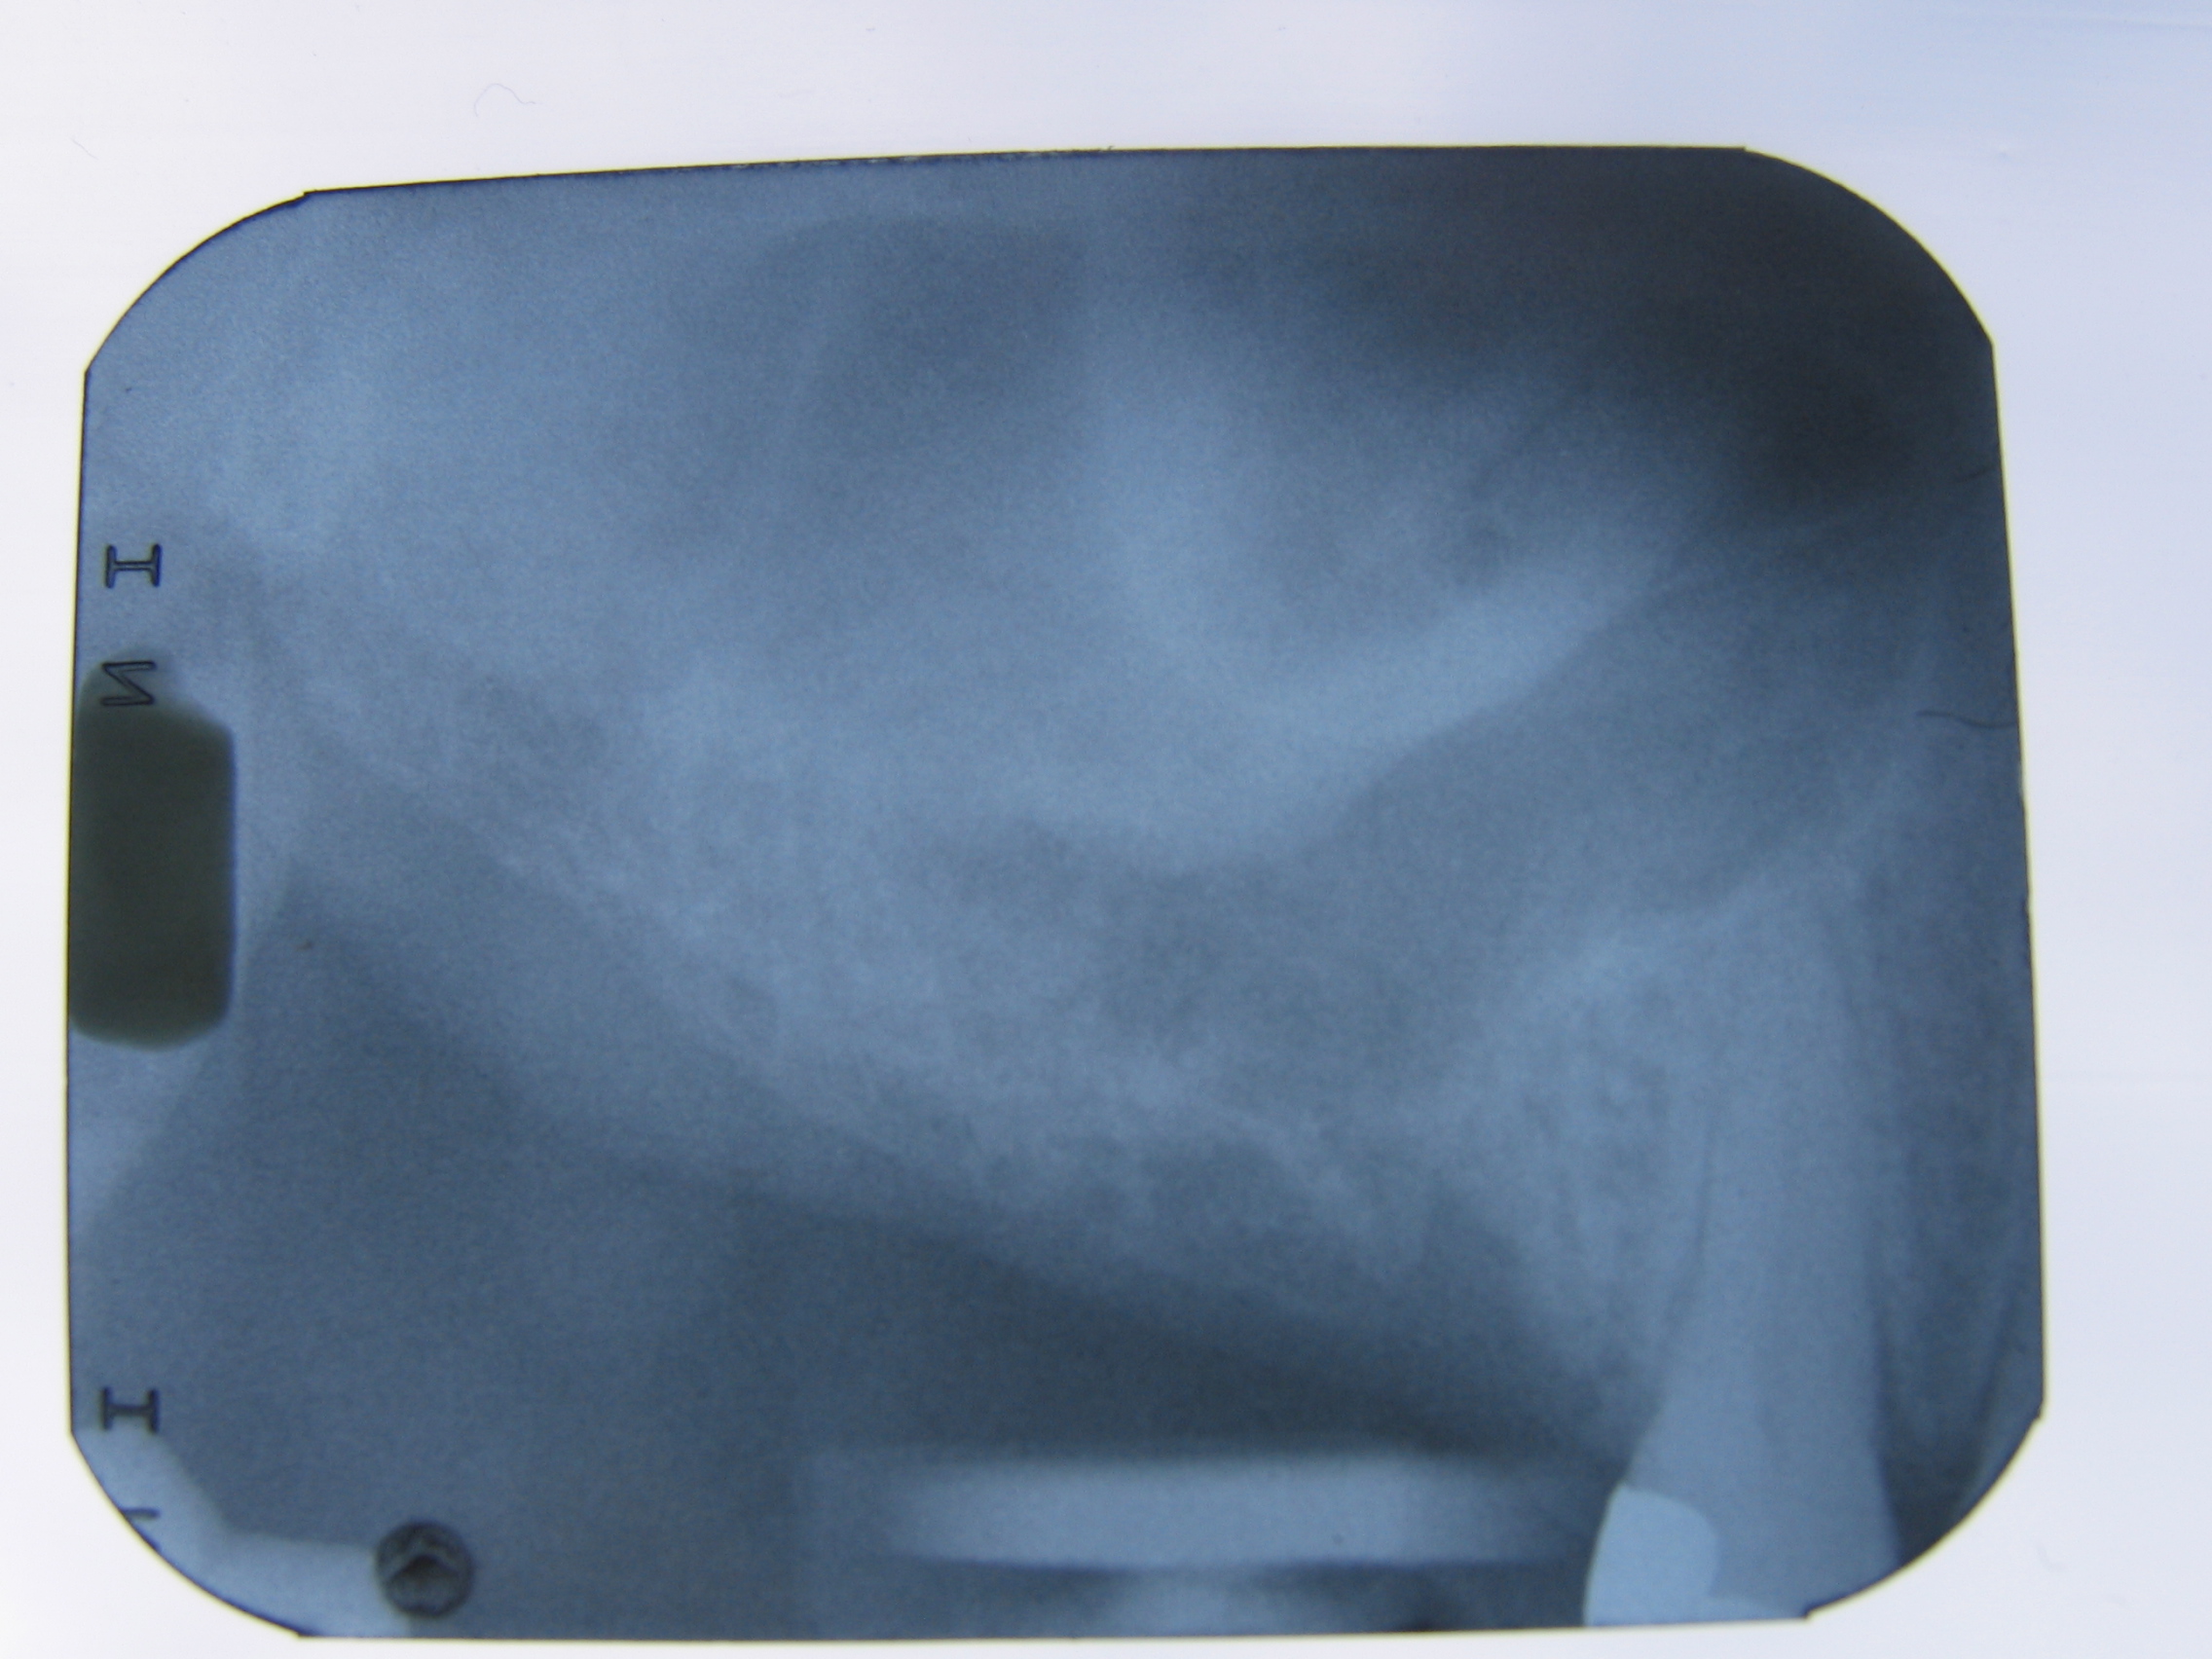

Ik heb hier een afbeelding van een 3D scan van de kaak,

en zou graag willen weten waarom de ene kant zwart is en de andere kant "mistig"…

Zie #1 en #2.

Sinusholte bij 1 laat sluiering zien.

De sinus kan vol vocht zitten,

de mucosa kan zodanig dik zijn dat de volledige sinusholte erdoor gevuld wordt; ook als het slijmvlies van de voorwand van de sinus zeer gezwollen is geeft dit een sluiering van de totale sinus; er kan agenesie van de sinus zijn. Bij totale sluiering is dus verder onderzoek vereist.

Flink uitgezakte sinus.

Hoe was de blaas/snuit proef?

Daar heb je gelijk in, bij mijn zus dus ook. Zij ging met het idee dat er nu eindelijk iets op die plek in haar kaak ging gebeuren naar de pijnpoli toe en kwam teleurgesteld terug met een recept. Ik heb voor haar verder gezocht en een andere pijnkliniek gevonden, waar ze misschien wel de zenuw aan kunnen pakken of blokkeren. Nog een vraagje, je zei een flink uitgezakte sinus, kan zoiets geen druk op een zenuw veroorzaken? Op de scan loopt de sinusholte, het zwarte gebied als ik het goed begrijp, ver naar beneden door, en dat is precies de plek waar het gevoelig is.